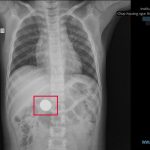

Sau khi thăm khám, các Bác sĩ nhanh chóng chỉ định thực hiện các cận lâm sàng cần thiết, CT scan bụng và ghi nhận dịch ổ bụng lượng vừa, rách gan độ III kèm dấu thoát mạch ở hạ phân thùy VII. Bệnh nhân được chỉ định Can thiệp mạch máu nút động mạch gan cầm máu cấp cứu. Sau 30 phút can thiệp, ekip Can thiệp mạch máu phối hợp cùng ekip phẫu thuật Gan và ekip phẫu thuật mạch máu đã tiếp cận và nút mạch thành công. Hiện tại bệnh nhân vẫn được theo dõi và tiếp tục điều trị tích cực, tạm thời đã qua cơn nguy hiểm.